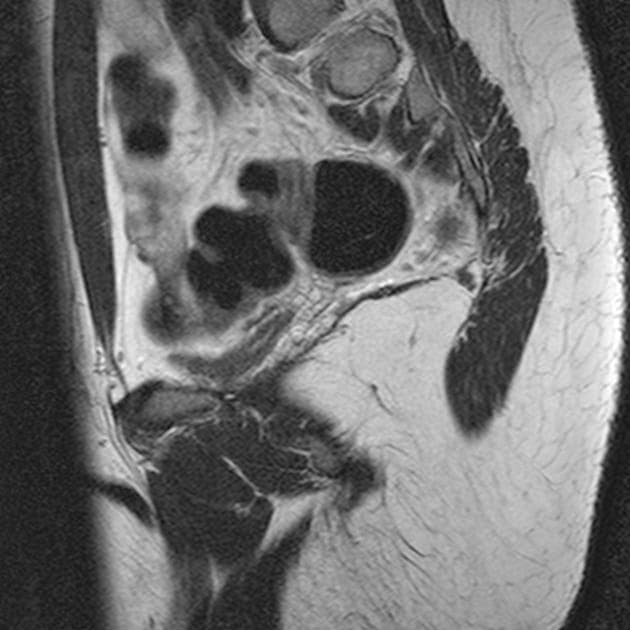

Axial FLAIR

- Vùng tín hiệu bất thường dạng không đều trên hình ảnh cộng hưởng từ trọng T2 và FLAIR, kèm dày lớp dưới vỏ và rãnh não nông ở thuỳ đỉnh – thái dương phải, lan tới vùng quanh tam giác của não thất bên cùng bên

- Lượng chất xám dưới biểu mô tăng bất thường dọc theo thành bên của sừng thái dương và vùng quanh tam giác não thất bên phải, gây hình ảnh uốn lượn thành não thất

- U nang màng nhện lớn ở thuỳ thái dương trước trái

- Thể chai (corpus callosum) bình thường

- Không có bằng chứng của hạn chế khuếch tán (restricted diffusion) ở bất kỳ vùng nào của não